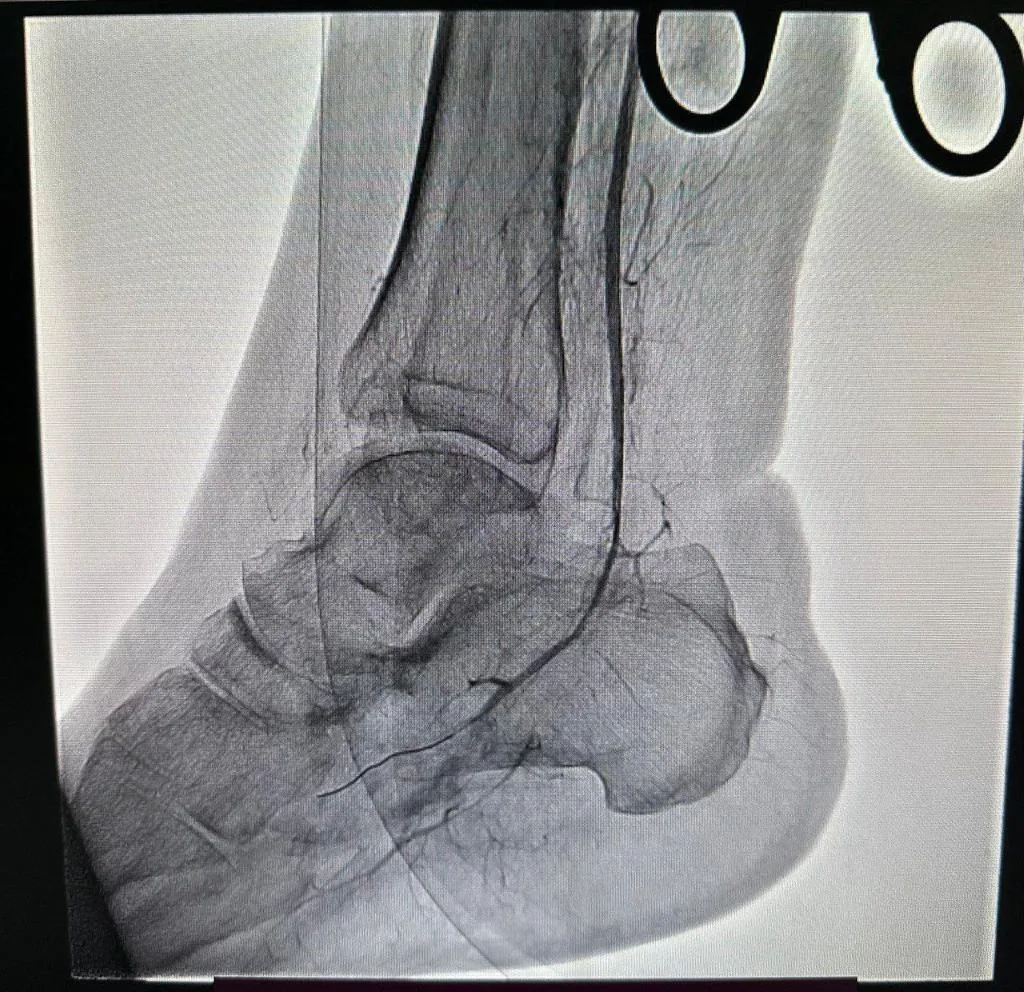

Після дообстежень – КТ-контрасної ангіографії нижніх кінцівок — виявили тромбоз підколінної та гомілкових артерій.

“Я взяв пацієнта на гібридне втручання: відкрите (тромбектомію – видалення тромбів із артерій) та ендоваскулярне, — продовжує розповідь Микола Федорів. — Це було поєднання відкритої хірургії та ендоваскулярної методики: ми розкриваємо судину, забираємо тромби, пускаємо контраст – і оцінити прохідність, побачити, чи є стеноз, звуження або атеросклеротичні бляшки”.

Після повторної тромбектомії лікарі ендоваскулярно відновили кровотік безпосередньо до стопи, де виявили закриту судинку. Після тривалого втручання вдалося пройти та знайти правильний хід, а тоді провели ангіопластику (роздування судини).